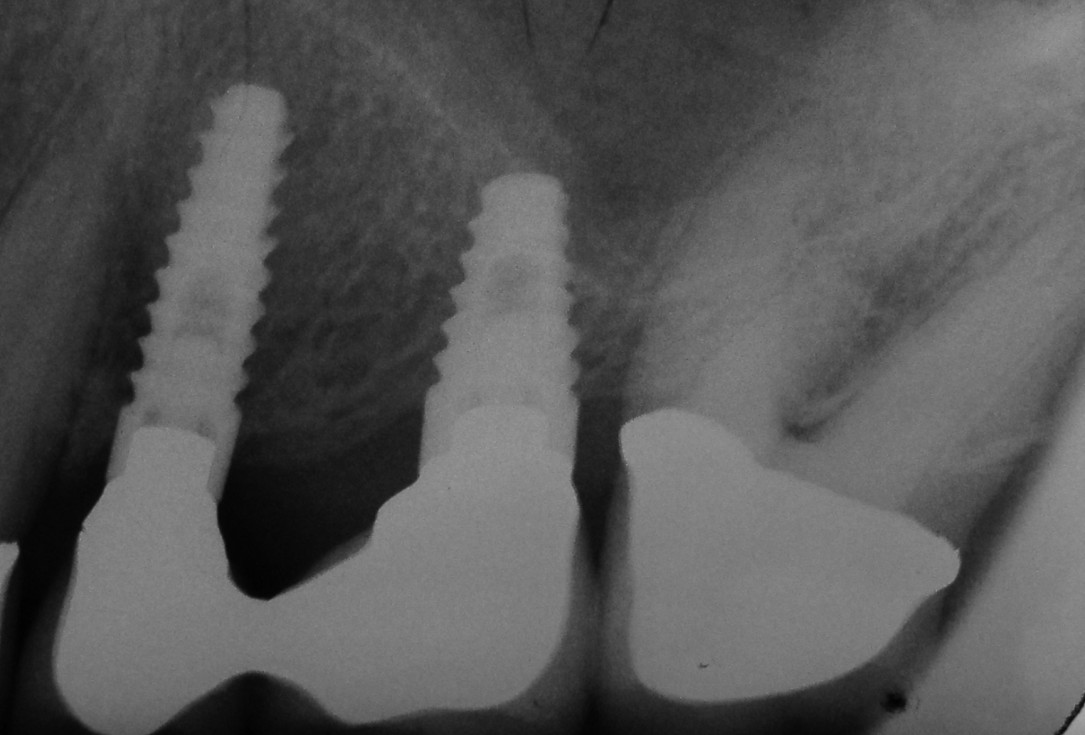

01/06 - Pre-operative radiograph.Treatment of a periodontal bone defect adjacent to an edentulous site using Straumann® Emdogain® - Prof. Dr. P. Windisch

06/06 - Radiograph 5 years post-operative.Treatment of a periodontal bone defect adjacent to an edentulous site using Straumann® Emdogain® - Prof. Dr. P. Windisch

Radiographic view before periodontal regenerative therapy with Straumann® Emdogain®. A deep intrabony defect appeared mesially and distally on the left mandibular first premolar. Pre-surgical probing measured 8 mm. The defect morphology presented as well-contained.

Pre-operative radiograph. Intrabony defect on the mesial aspect of tooth 14.